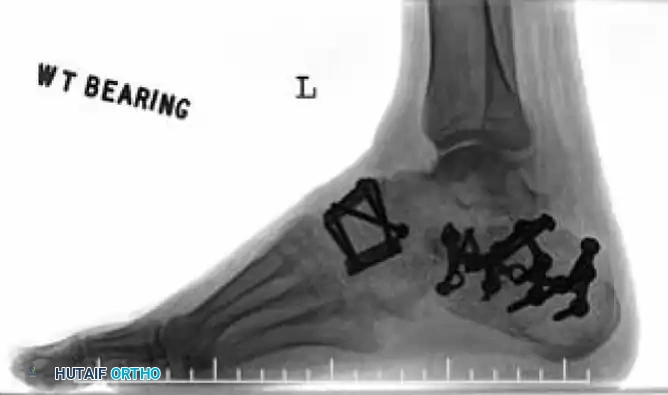

Clinical Evaluation and Radiographic Parameters

Any injury resulting in midfoot tenderness, swelling, or an inability to bear weight merits rigorous evaluation.

Radiographic Evaluation:

Standard non-weight-bearing radiographs often miss subtle instability. Weight-bearing radiographs are absolute requirements if the patient can tolerate them. If the patient cannot bear weight, a short-leg cast should be applied for 10-14 days, followed by repeat weight-bearing films.

Key radiographic parameters to evaluate:

1. The medial shaft of the 2nd metatarsal must align perfectly with the medial aspect of the middle cuneiform on the AP view.

2. The medial shaft of the 4th metatarsal must align perfectly with the medial aspect of the cuboid on the oblique view.

3. The 1st metatarsal-cuneiform articulation must show no incongruency.

4. The "Fleck Sign": Look for a small bony avulsion in the space between the medial cuneiform and the base of the 2nd metatarsal. This represents a bony avulsion of the Lisfranc ligament.

5. Evaluate the naviculocuneiform articulation for subtle subluxation.